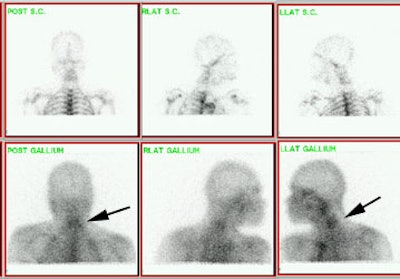

Gallium imaging for vertebral osteomyelitis: The patient below had an extensive cervical spine osteomyelitis involving C4 to C6. A pre-contrast MR image is shown on the left (degraded by motion), and a post-gadolinium image is shown in the center. Gallium-67 imaging revealed increased tracer activity corresponding to the area of abnormality on MR (black arrow) and was going to be used to monitor response to therapy. SPECT imaging would have been beneficial, but the patient could not tolerate the exam. Note the photopenic defect in the area of infection on corresponding Tc99m-sulfur colloid images (top row of nuclear medicine images). |

|